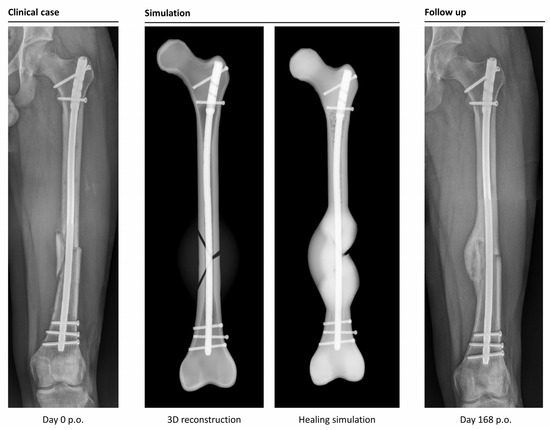

The simulation classified 26 cases as “healing”, while it categorized 6 cases as non-unions. In retrospective comparison with the clinical outcomes, the simulation correctly predicted 23 uncomplicated healing fractures. Three patients would have been expected to heal according to the simulation, but clinically turned out as non-unions (false negatives). Four out of six predicted non-unions were correctly recognized by the simulation, but two cases were wrongfully diagnosed as developing non-unions (false positives). This means the simulation correctly predicted the right outcome in 85% of the cases (Figure 4 and Figure 5).

To compare virtual and clinical outcomes, the mRUST score was evaluated for all cases. “Healing” was defined as the first time an mRUST score over 9 was reached, which means a bridging of at least 3 cortices. The mean mRUST score was 9.5, whereas the time of follow-up X-rays varied in such a range that no direct comparison is possible (Figure 6).

Figure 4. Example of a correctly simulated, healing fracture. The postoperative X-ray (picture 1, left) is used to build a 3D reconstruction (picture 2). The simulation correctly predicts uncomplicated healing (picture 3). A retrospective comparison to a follow-up X-ray on day 168 after surgery shows similar callus formation and progressing consolidation (picture 4, right).